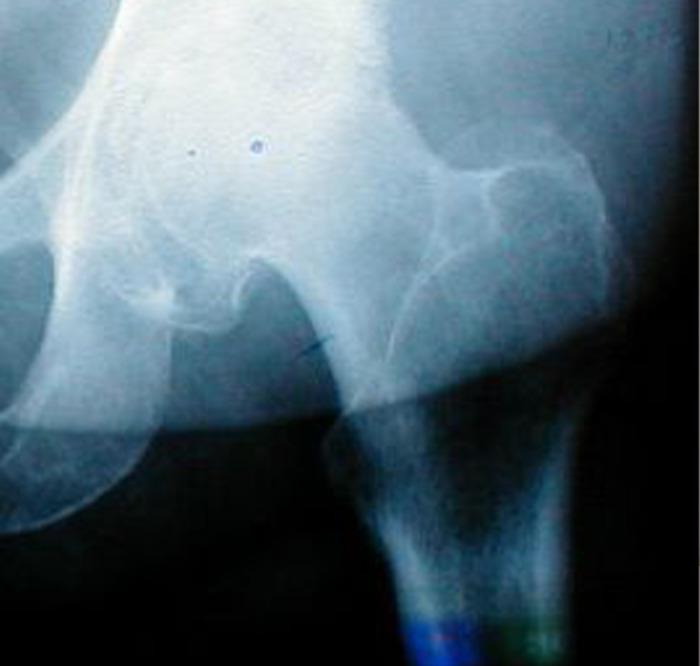

My grandmother had her hip replaced, but the hip always hurt to her. She waited a year, hoping it would go away but it never did, she asked multiple doctors and did multiple x-rays but doctors said the replaced hip was fine. We finally made her go to a private clinic in my hometown, and the doctor saw that the replaced hip was fine and dandy, but the bone around it looked like it was a tad bit eaten by bacteria.

So the new doc did an operation, and there was so much pus in the leg it was insane. If my grandmother waited any longer, her blood would become infected and she would have died.

Thank goodness she went to the clinic.